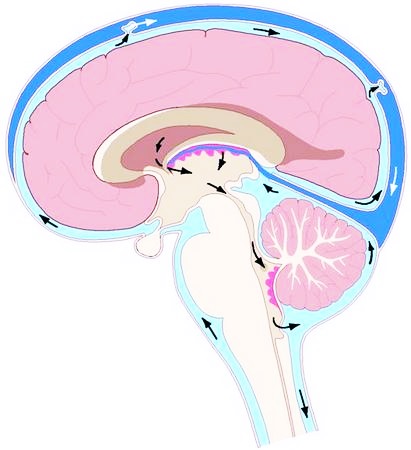

Киста – это образование в прослойке, располагающейся между тканями. Дословно этот термин означает «пузырек». Ее заполняет эпидермий или жидкость. Мы расскажем, что такое ликворная киста головного мозга, почему образуется, какие виды ее бывают, как с ней бороться.

Полость ликворной кисты заполнена спинномозговой жидкостью. Она может образоваться из рубца или родной ткани. По размеру – это крошечное новообразование, которое трудно разглядеть даже при помощи МРТ.

- Локализация. Арахноидальная киста головного мозга расположена между мягкой тканью и оболочкой. Церебральная – непосредственно в ткани мозга. Арахноидальная ликворная киста редко дает симптомы. Это объясняется тем, что субарахноидальная киста не затрагивает непосредственно сам мозг, а расположена между ним и внешней оболочкой.